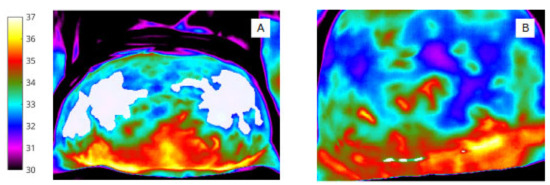

However, identifying one (or more) surface anatomy regions of interest (ROI) from the heat map is both labour-intensive and subjective, as is the refining and ‘fine-tuning’ of pixel level features. Problems emerge due to ‘crowding’ of objects, whereby pixel features are not easily assigned to the ‘correct’ bounding box or cluster group [14]. When overlap occurs between ROIs (such as that shown in Figure 1) [15], feature extraction from a specific ROI can be difficult and lead to misclassifications. To improve upon the reliability of our existing, manual, image post-processing and wound outcome modelling undertaken by a single, experienced researcher (CC) and reported previously [3], our overarching objective was to use the acquired images to refine and improve scope in image analysis using AI-based segmentation.

Figure 1.

An illustration of overlapping ROI masks.

The manual segmentation procedure was performed in MATLAB (R2020a: Mathworks). The image labeller application was used to annotate each ROI label via pixel-level segmentation and creation of pixel masks for the series of 50 abdominal (Figure 1) and wound sites (Figure 2). The segmentation process was performed by two independent researchers, ‘blinded’ to the segmentation process of the other, and was broadly achieved in two stages to

Figure 2.

(A) Infrared image showing segmentation of the abdomen (ROI 1) and white bounding box. (B) Binary mask of abdomen (ROI 1).